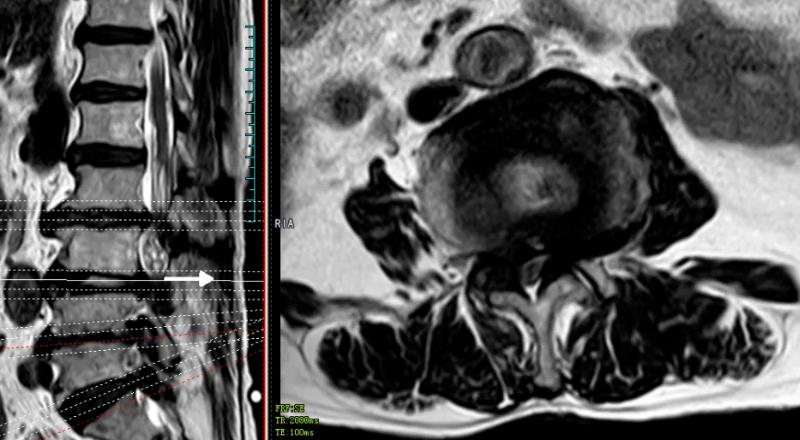

文章配圖

△磁共振提示胸10、胸12、腰1椎體壓縮性骨折,胸9/10、胸10/11黃韌帶骨化、椎管嚴重狹窄。

經過脊柱外科團隊的多次討論,為魯婆婆制定了個體化治療方案。于今年7月5日,在麻醉科的監護下,脊柱外科姚仕奮主任團隊成功為魯婆婆開展手術,術后經過藥物治療及指導患者功能康復鍛煉,魯婆婆可自行行走,順利出院。